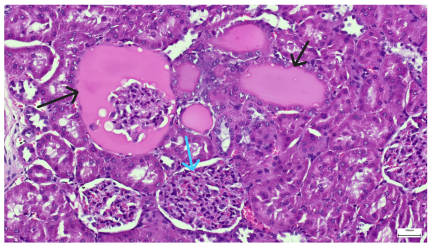

| 4.5. Trichrome Masson stain, 100× magnification, 200 microns scale segment. Arteriole wall thickening (green), unequal glomerular size and basal membrane thickening (blue), extensive proximal renal tubule basal membrane thickening (black), pronounced fibrosis in renal parenchyma (yellow). Group III diabetic and normal-diet-fed specimens. | 4.6. Hematoxylin and Eosin stain, 100× magnification, 200 microns scale segment. Glomerular congestion, hyaline material present inside the lumen of renal tubules, flattened tubular walls. Group III diabetic and normal-diet-fed specimens. |